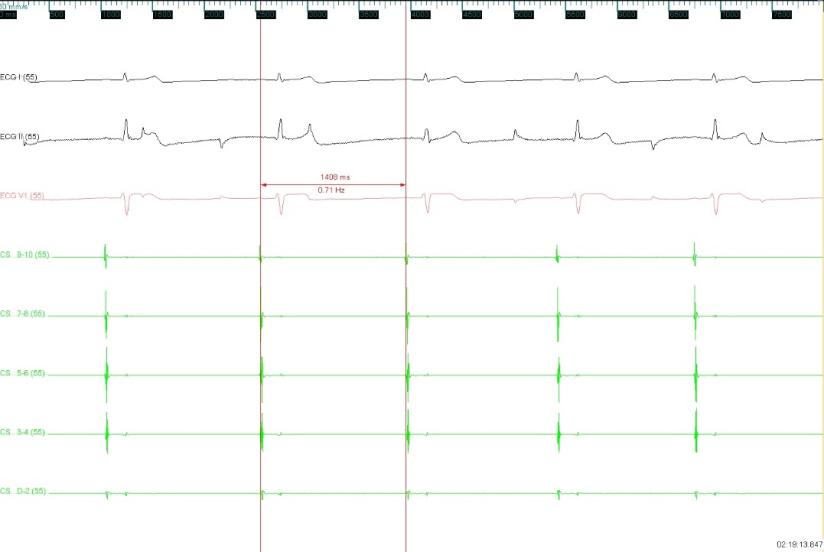

图1 术前心率43次/分